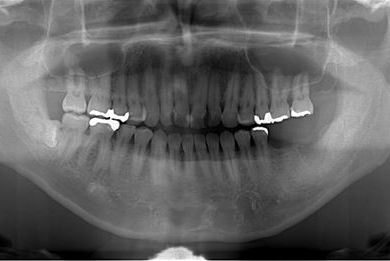

| 性別/年齢 | 男性 / 32歳 | ||||||||||||||||||||||||||||||||

| 主訴 | 銀歯がはずれたところの治療と、インプラント治療相談。 | ||||||||||||||||||||||||||||||||

| 治療方針 | 欠損部分をインプラント治療により、機能的・審美的回復を行う。 | ||||||||||||||||||||||||||||||||

| 治療内容 | インプラント2本、ハイブリッドセラミッククラウン2本 | ||||||||||||||||||||||||||||||||

| 総治療費 | 399,000円 | ||||||||||||||||||||||||||||||||

| 治療期間 | 7ヶ月 |

インプラント埋め込み施術は外科治療のため、腫れる可能性があります。細菌感染すると施術のやり直しになりますが、当院では洗浄・滅菌を徹底して感染リスクを抑えます。また、インプラント周囲炎にならないために、通常の歯と同じように丁寧なブラッシングや定期メンテナンスが重要となります。